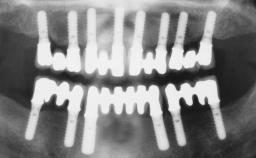

Immediate Loading of Four Implants in the Mandible and Final Restoration with a Full-Arch Metal Framework FDP

A fully edentulous 65-year-old woman was referred to our clinic for esthetic and functional dental rehabilitation. The patient presented with inadequate complete maxillary and mandibular prostheses, insufficient vertical dimension, and extensive tooth wear. The clinical examination and anamnesis showed no local or systemic contraindications, no signs or symptoms of bruxism, and an absence of smoking habits. The treatment proposed was implant placement in the mandibular interforaminal area and immediate loading with a fixed definitive prosthesis. A removable mucosa-supported complete prosthesis was indicated for the upper jaw, since its bone structure offered satisfactory retention and the financial condition of the patient disfavored a full-mouth implant-supported rehabilitation.

# of Implants 4

Type of Implants One-Piece

Loading Protocol Immediate

Retention Screw-retained, with 4 or more splinted implants Screw-retained, with 4 or more splinted implants